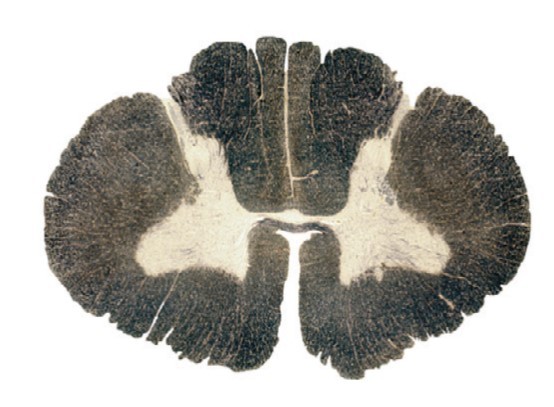

Q

The region highlighted corresponds to the territory of which artery/pair of arteries?

Anterior spinal

Medullary

Posterior spinal

Vertebral

A